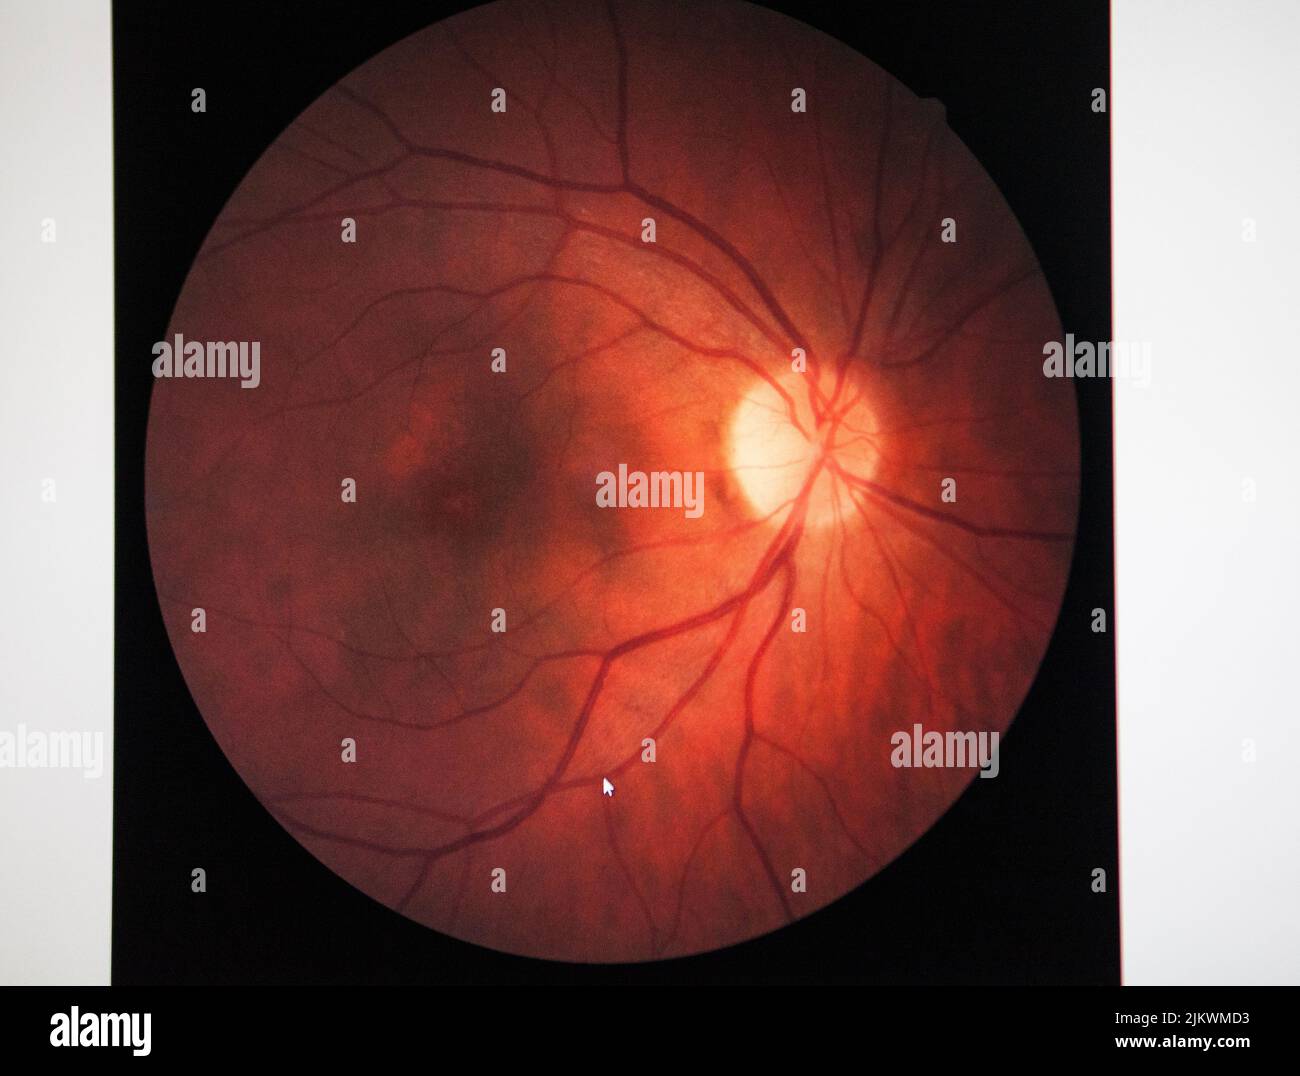

Fundus of a patient with macular edema. Stock Photohttps://www.alamy.com/image-license-details/?v=1https://www.alamy.com/fundus-of-a-patient-with-macular-edema-image476923247.html

Fundus of a patient with macular edema. Stock Photohttps://www.alamy.com/image-license-details/?v=1https://www.alamy.com/fundus-of-a-patient-with-macular-edema-image476923247.htmlRF2JKWMD3–Fundus of a patient with macular edema.